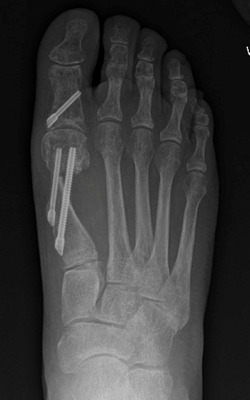

TOTAL ANKLE REPLACEMENT :: ORIF CALCANEUS :: ORIF ANKLE FRACTURE DISLOCATION :: COMPLEX BUNION AND LESSER TOE CORRECTION :: TALUS FRACTURE -1 :: TALUS FRACTURE -2 :: LISFRANC REPAIR :: COMPLEX TRIPLE ARTHRODESIS 1 :: COMPLEX TRIPLE ARTHRODESIS 2 :: MINIMALLY INVASIVE BUNION REPAIR 1 :: MINIMALLY INVASIVE BUNION REPAIR 2 :: ARTHROSCOPIC CARTILAGE REPAIR :: TENEX SPUR DEBRIDEMENT :: Haglunds Debridement and Achilles Repair